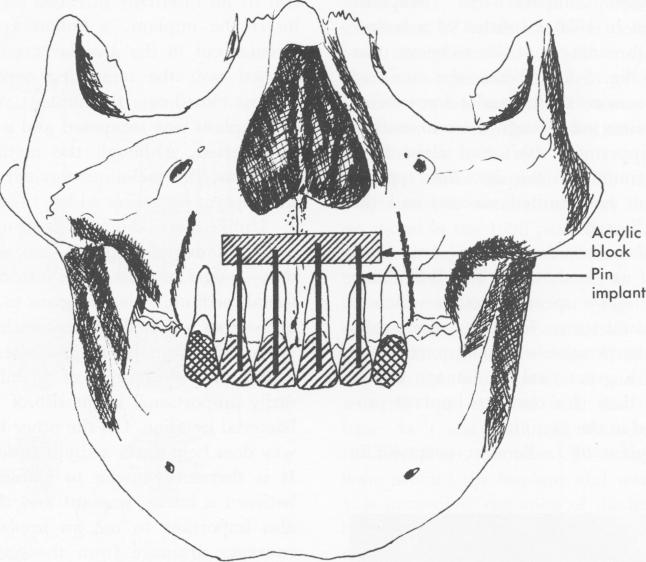

Fig. 5-55. Raphael Chercheve placed an acrylic block over the anterior teeth and drove pins through the canals into the block. Since it was difficult to execute, the procedure has been discarded. (From Linkow, L. I.: Clinical evaluation of the various designed endosseous implants, J. Oral Implant Transplant Surg. 12:42, 1966.)

1 Chercheve upper endosseous pin implant from root canal to acrylic block